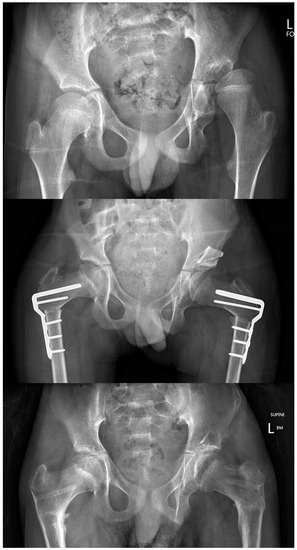

17. Scoliosis and Pelvic Obliquity

18. Femoral Head Deformity: Salvage or Reconstruction?

19. Palliation of CPHD and the Role of Salvage Surgery